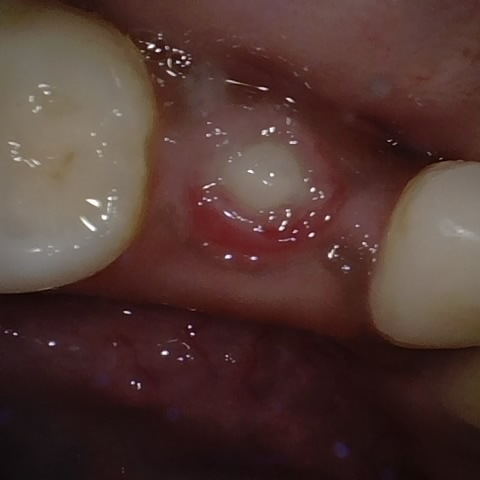

Annotated as "Good"